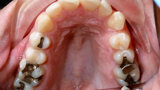

ClearCorrect treatment of crowding